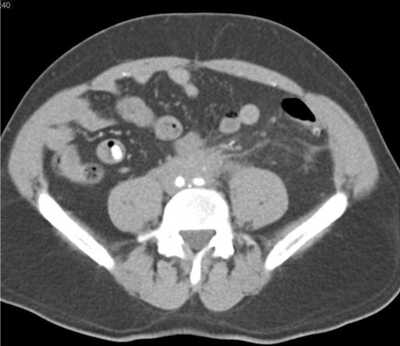

A 59-year-old man presented with right loin pain. His GP arranged for him to have an intravenous urogram (IVU) and subsequent CT urogram performed.

Retroperitoneal fibrosis. Proximal hydronephroureterosis, tapering of the ureteric lumen and medial deviation of the ureter.